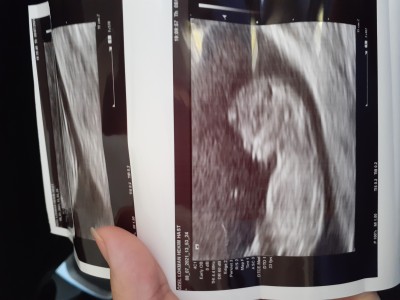

Geçen hafta bağdaş kurmuştu göremedik. Çikolata ye dediniz yedim şimdi de yerinde durmadı göremedik. Bilenler tahmin lütfen

Sanırım dünde atmıştın  hiç belli deil ama kız  a benziyor kemik yapisi

12 haftalık canım yok görmeme izin vermiyor dedi çok oynadi

Nub teorisine gore kız sanirim allah hayirla kucaginiza almanizi nasip etsin